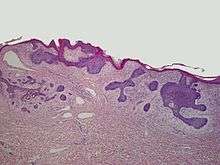

Basaloid follicular hamartoma

A basaloid follicular hamartoma is a cutaneous condition characterized as distinctive benign adnexal tumor that has several described variants.[1]:675